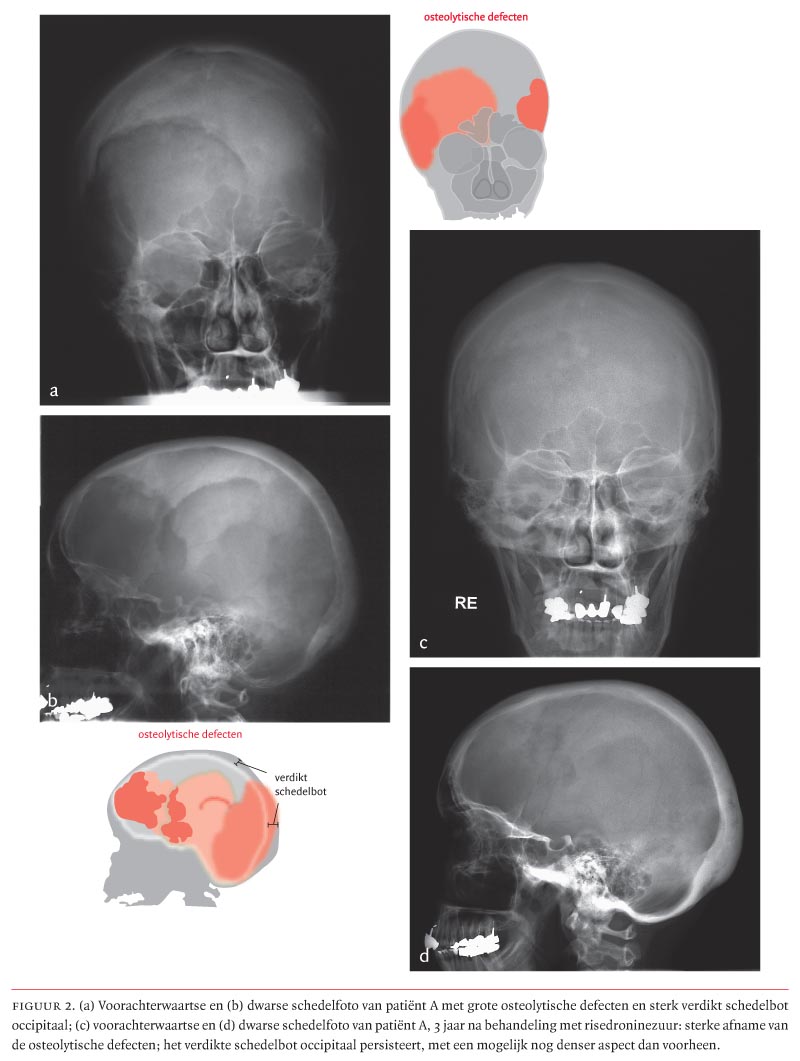

Ziekte van Paget. Osteïtis deformans. Vervormingen en verdikkingen van het bot door verhoogde botafbraak en -aanmaak. Komt vooral voor in bekken, wervelzuil, dijbeenderen en schedel. Op deze pagina. Afspraken. Symptomen. Behandeling. Onderzoeken en diagnose. Specialisten. Afspraken. Centrum voor metabole botziekten.. Leeftijd. Voorgeschiedenis van borstkanker of borstafwijkingen. Familie met borstkanker. Genetische factoren. Dicht borstweefsel. Blootstelling aan straling. Overgewicht. Hormoonvervangingstherapie. Alcohol. Symptomen van de ziekte van Paget. Schilfering van de tepelhuid en ingetrokken tepels. Hard knobbeltje in de borst. Onderzoek en diagnose.